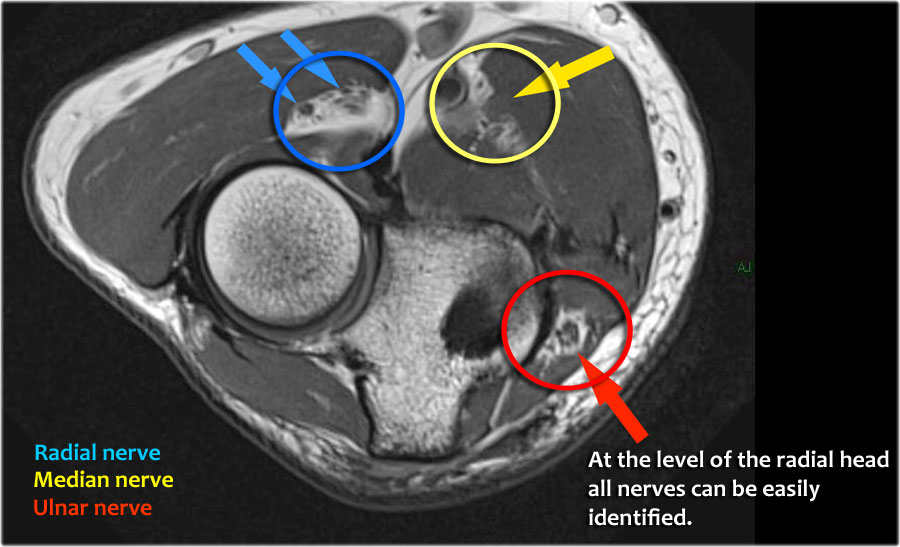

Dây thần kinh quay có thể được xác định rõ nhất ở mức chỏm xương quay, nơi có thể quan sát thấy các nhánh nông và nhánh sâu trong ống xương quay (mũi tên).

This is a very consistent place to find the radial nerve.